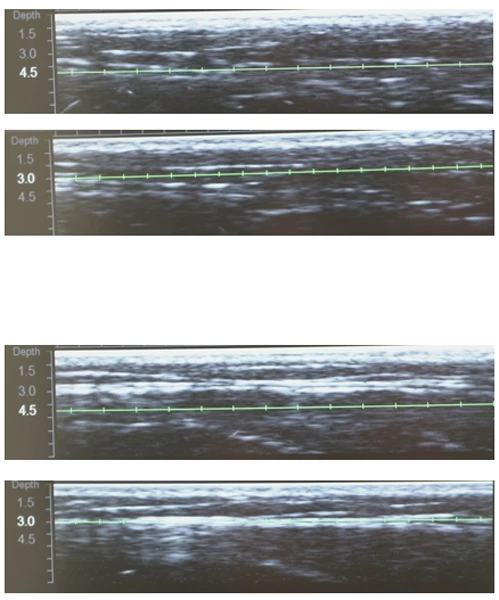

Диагностическая визуализация щёчной, периоральной и периорбитальной зон. Протокол лечения: DS 7–4,5 70 линий; DS 7–3,0 402 линии; DS 10–1,5 192 линии. Суммарно все лицо: 850 линий.

Диагностическая визуализация субментальной зоны. Протокол лечения: DS 4–4,5 97 линий; DS 7–3,0 110 линий. Суммарно все лицо, включая субментальную зону: 871 линия.